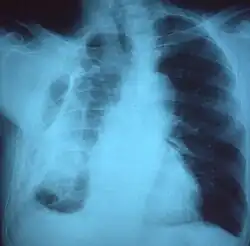

Chest x-ray showing fibrous opacity on one side

Fibrothorax on chest x-ray

A fibrothorax can typically be diagnosed by taking an appropriate medical history in combination with the use of appropriate imaging techniques such as a plain chest X-ray or CT scan.[3] These imaging techniques can detect fibrothorax and pleural thickening that surround the lungs.[7] The presence of a thickened peel with or without calcification are common features of fibrothorax when imaged.[3] CT scans can more readily differentiate whether pleural thickening is due to extra fat deposition or true pleural thickening than X-rays.[3]

If a fibrothorax is severe, the thickening may restrict the lung on the affected side causing a loss of lung volume.[7] Additionally, the mediastinum may be physically shifted toward the affected side.[3] A reduction in the size of one side of the chest (hemithorax) on an X-ray or CT scan of the chest suggests chronic scarring.[6] Signs of the underlying disease causing the fibrothorax are also occasionally seen on the X-ray.[6] A CT scan may show features similar to those seen on a plain X-ray.[7] Lung function testing typically demonstrates findings consistent with restrictive lung disease.[6]